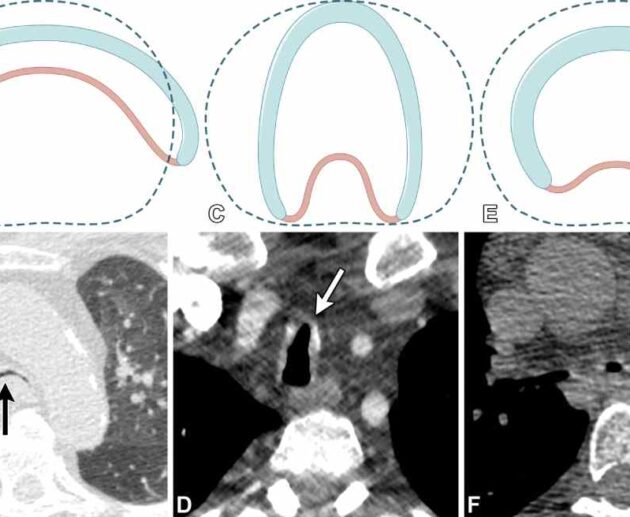

EDAC (Esophageal Dysphagia and Achalasia Care): Understanding the Disorder, Modern Treatment Approaches Achalasia is a rare but profoundly disruptive esophageal